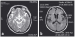

Abbildung 2a-b: Steele-Richardson-Olszewski-Syndrom MRT bei der zweiten Visite mit mittelliniennaher mesodienzephaler Raumforderung rechts: (a) T2/Flair-Horizontalschnitt auf dienzephaler Ebene; (b) T2- Sagittalschnitt mit mesodienzephalem Tumorödem |

MRT bei der zweiten Visite mit mittelliniennaher mesodienzephaler Raumforderung rechts: (a) T2/Flair-Horizontalschnitt auf dienzephaler Ebene; (b) T2- Sagittalschnitt mit mesodienzephalem Tumorödem |